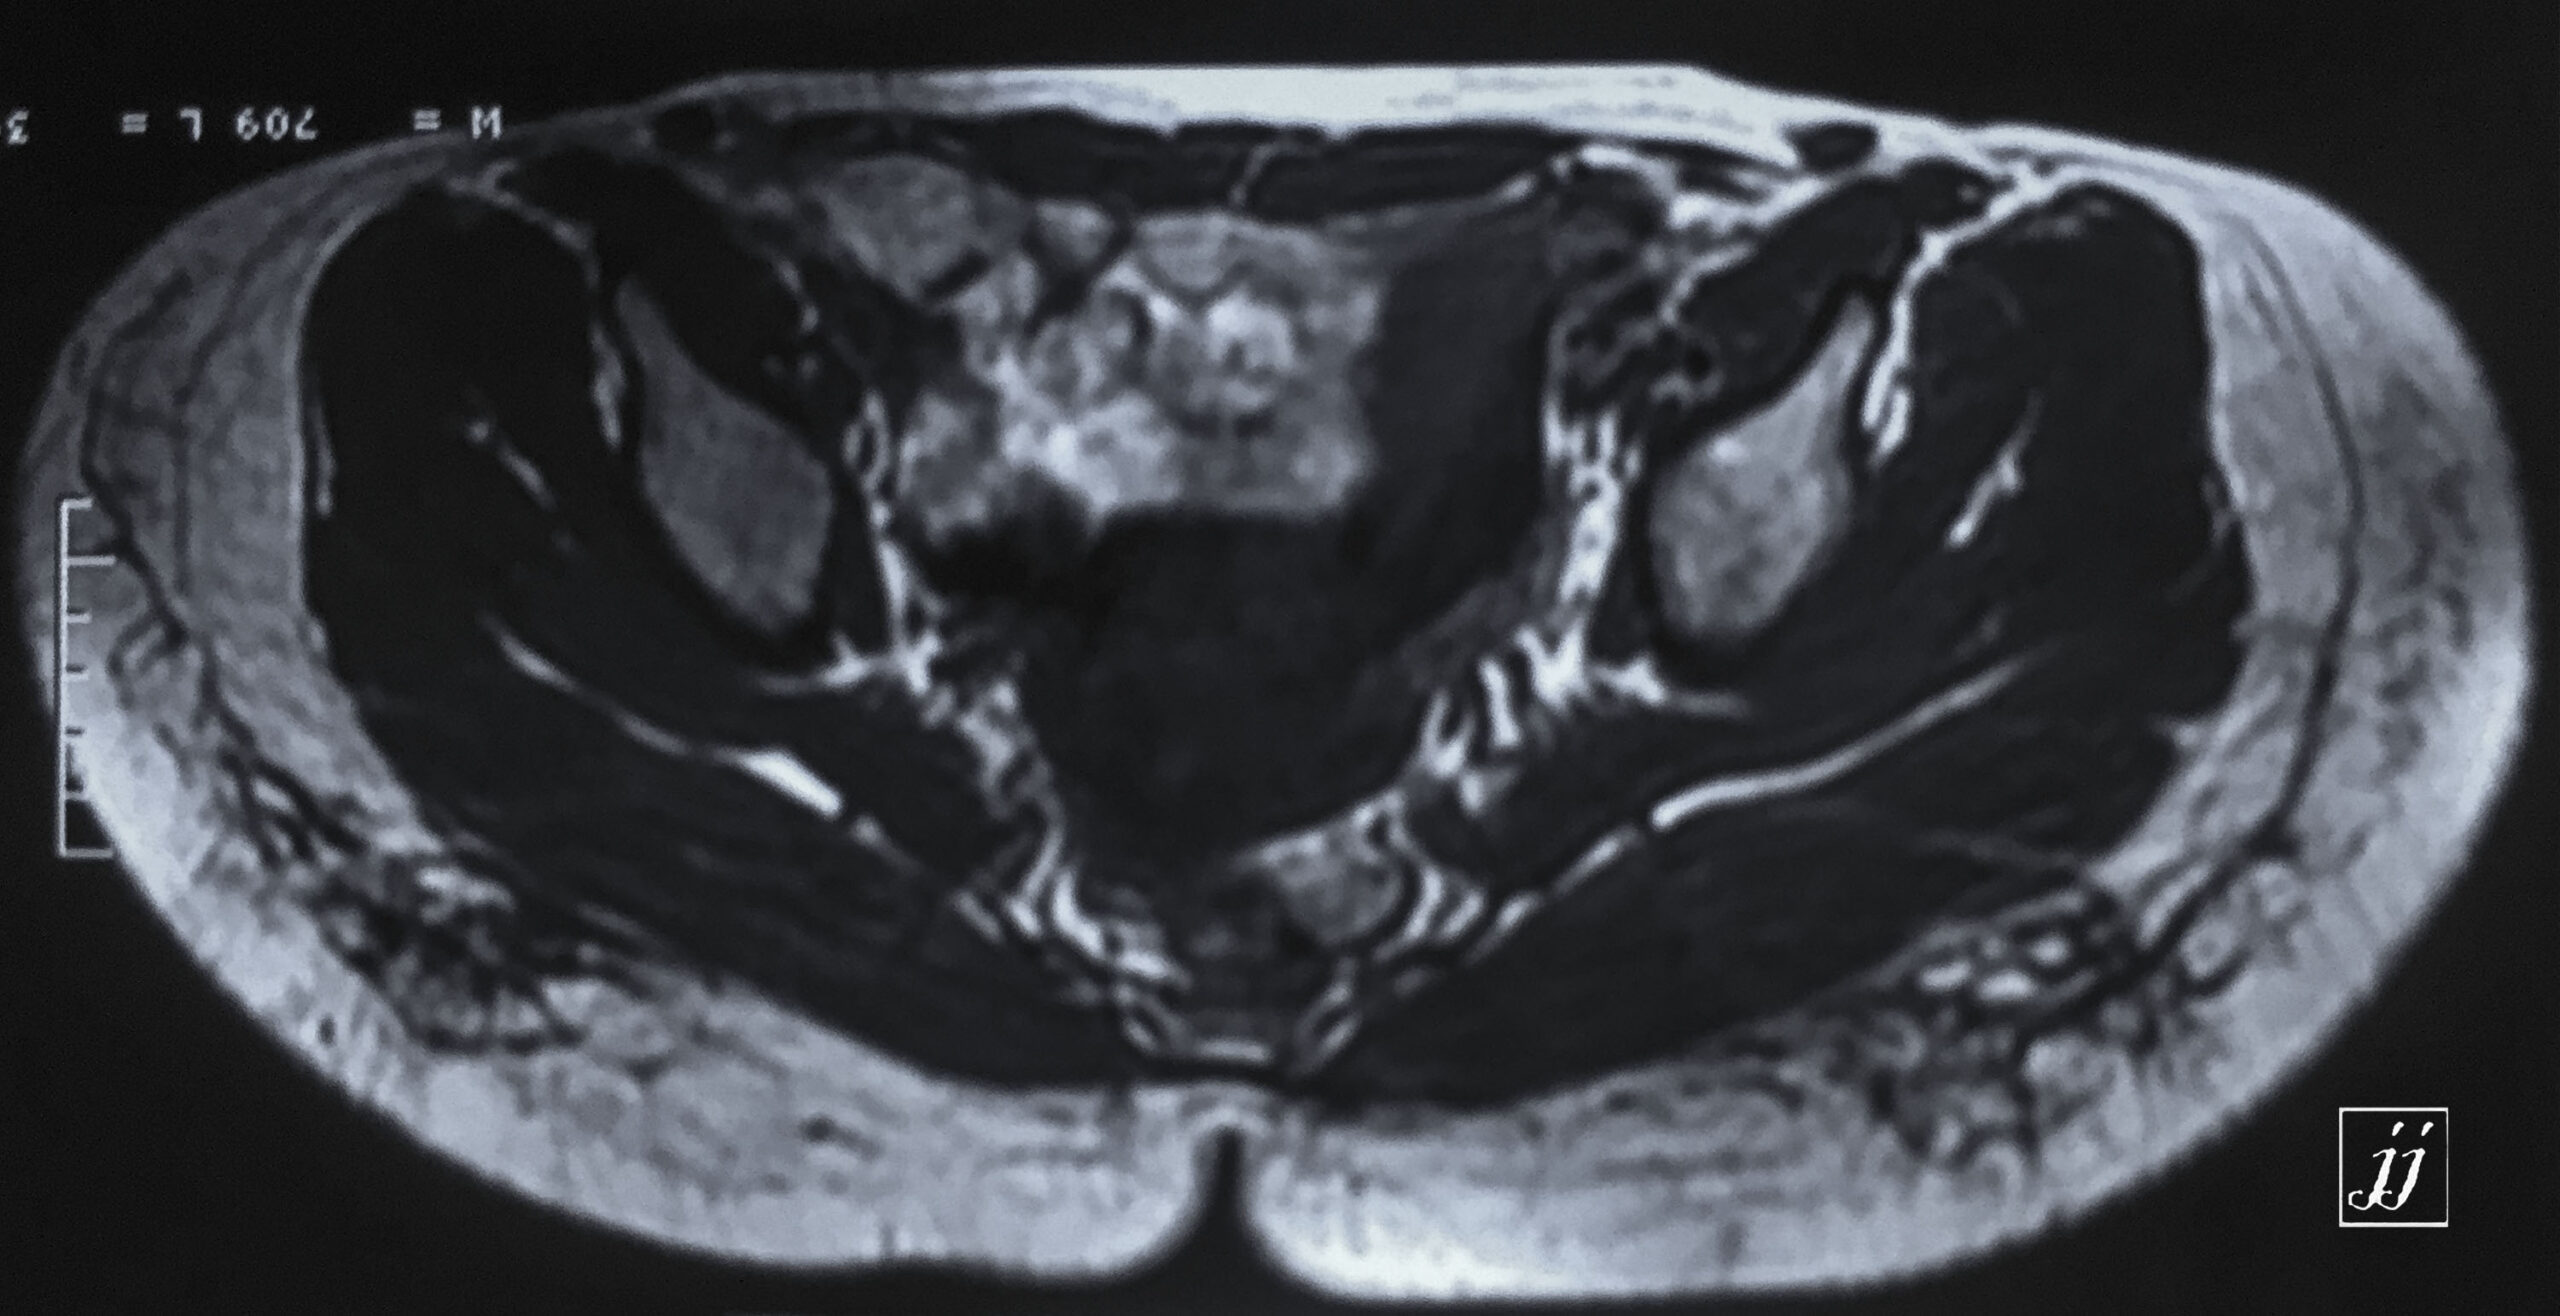

MSK- large intrapelvic mass (2)